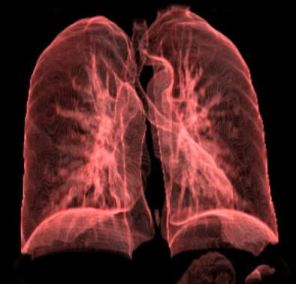

Zatürre (Pnömoni)

Bir veya birkaç akciğer lobunun iltihaplanması şeklinde ortaya çıkan bir hastalıktır. İltihaplanmaya virüs,bakteriler veya mantar gibi mikroorganizmalar sebep olmaktadır.Ayrıca alkol,uyuşturucu maddeler,sigara ve kötü hayat şartları zatürreye ortam hazırlayan faktörtörlerdir.